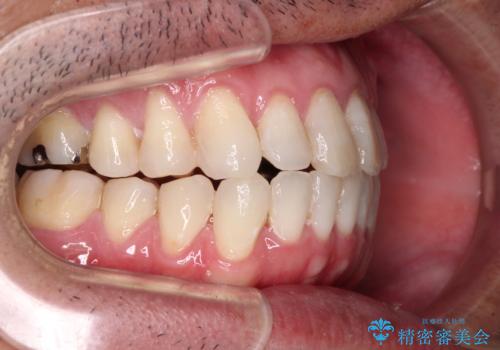

内側に転位した歯とボロボロのむし歯 インビザラインによる矯正治療とむし歯治療

- ボロボロのむし歯とデコボコの歯列を気にして来院された患者様です。

ボロボロとなっていた歯は抜歯が必要な状態でしたが、舌側転位している歯を移動させることで抜歯スペースを埋めることができるため、矯正治療により歯列を整えることとしました。

舌側転位の改善にインビザラインを用いるのはやや難易度が高くなりますが、前歯部のデコボコは軽度であったため、インビザラインによる矯正治療を行うこととしました。